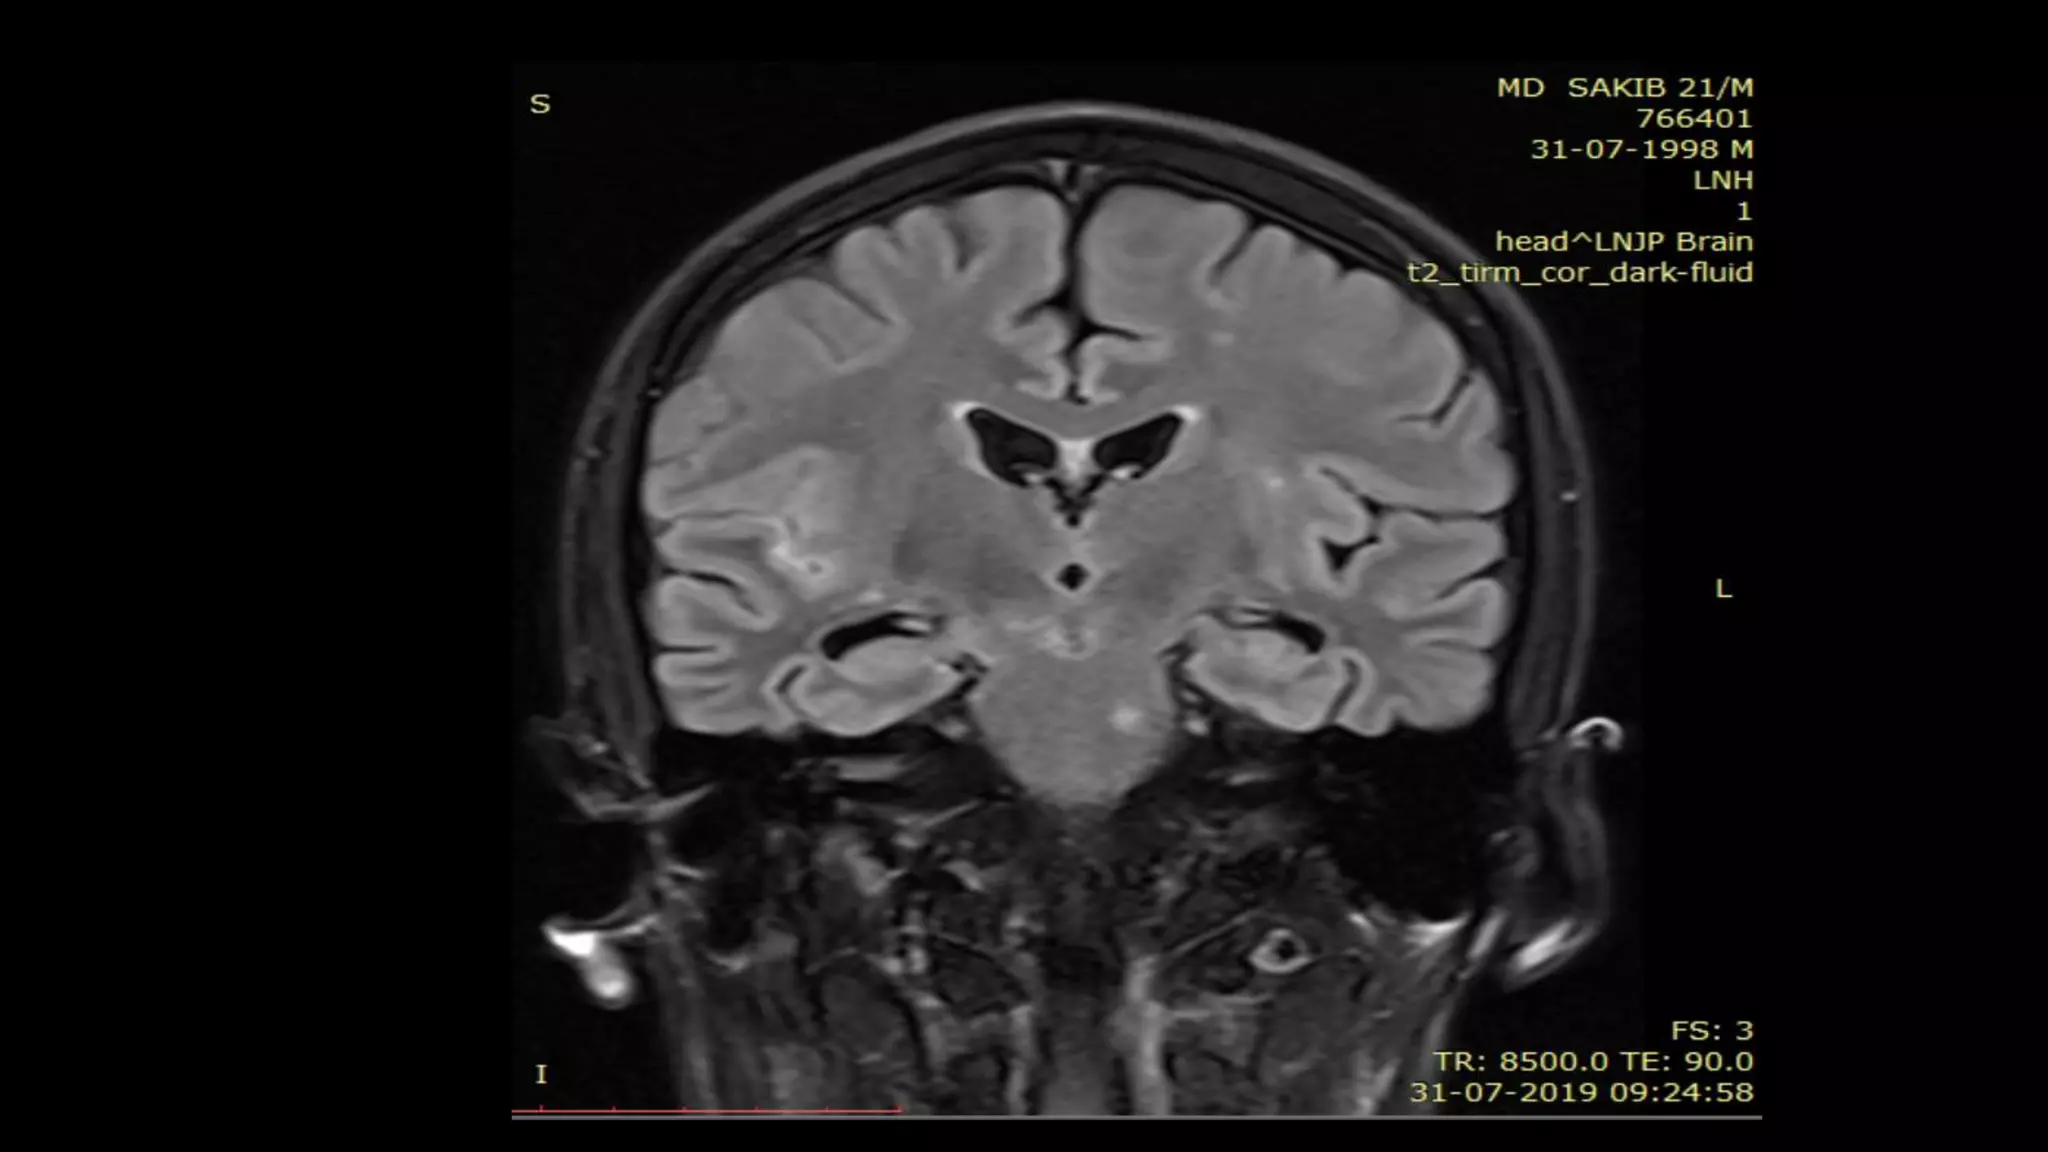

• #121 this are the axial FLAIR and DWI images showing another example of acute lacunar infarct in left hemispheric white matter showing FLAIR AND DWI hyperintensity

• #122 Follow csf signal